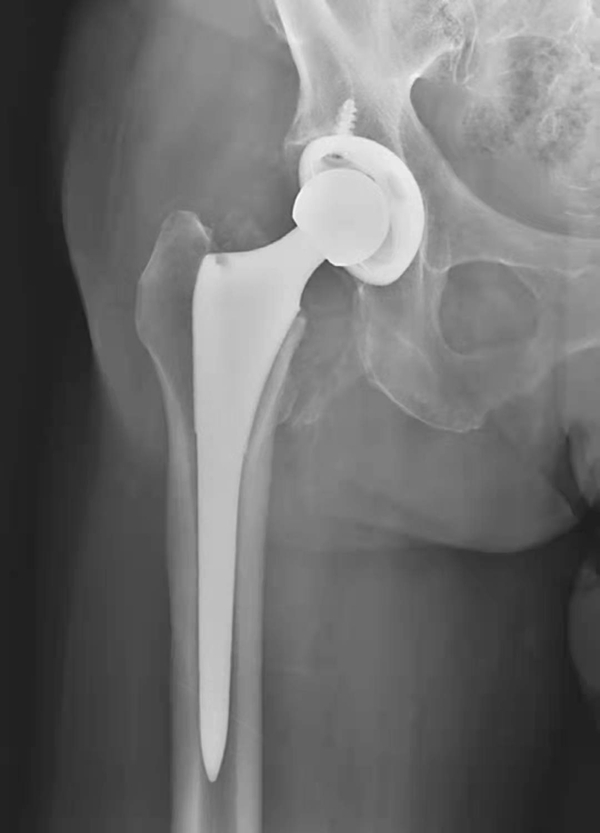

图9 人工髋关节假体移位伴脱位

X线片,示左侧髋臼杯松动,逆时针转位,俯倾角显著增大,人工股骨头向外上方移位,与髋臼失去正常对应关系